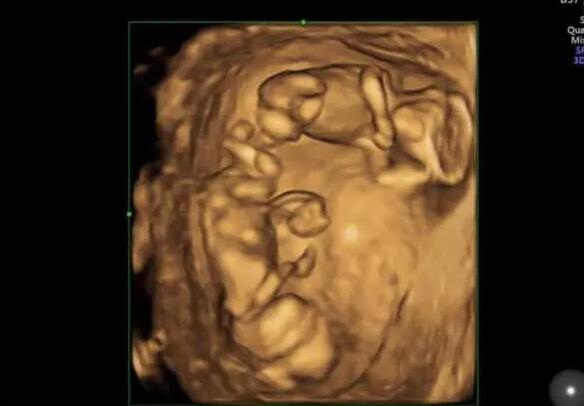

南京12345今日咨询热点,想咨询一下南京试管成功率高的私立医院有哪家?可以推荐一下吗?

想咨询一下南京试管成功率高的私立医院有哪家?可以推荐一下吗?

如果你只考虑在私立医院做试管南京私立三代试管医院推荐我建议你选择家恩德运医院南京私立三代试管医院推荐,医疗团队专业南京私立三代试管医院推荐,环境也还不错。需要可以百度搜下。